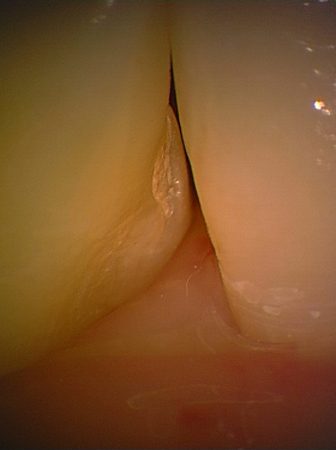

Einsatz des dünnsten Spatel der Welt (45mikron) im sonst anatomisch falsch gestalteten Zahnwischenraum

vorher